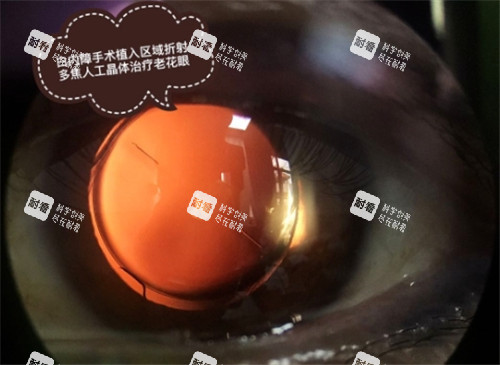

赤峰上京医院作为“彭年光明行动”定点机构,自2025年4月起启动免费白内障手术项目,重点针对合并糖尿病、高血压等代谢性疾病的患者。

符合条件的低收入患者可申请全免费手术,包括晶体植入、术后用药等全部费用。